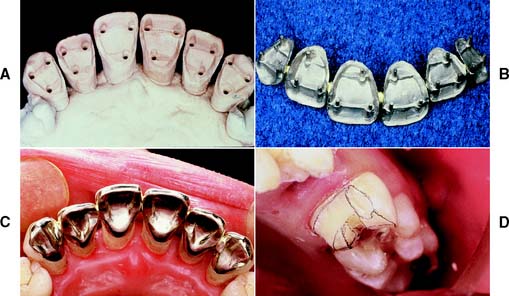

A metal matrix band around the adjacent tooth for protection may be helpful; however, the thin band can nonetheless be perforated and the underlying enamel damaged. The preferred method is to use the proximal enamel of the tooth that is being prepared for protection of the adjacent structures. Teeth are 1.5 to 2 mm wider at the contact area than at the cementoenamel junction. Therefore, a thin, tapered diamond can be passed through the interproximal contact area (Fig. 7-2) to leave a slight lip or fin of enamel without resulting in excessive tooth reduction or necessitating undesirable angulation of the rotary instrument. The latter situation, tipping the diamond unnecessarily away from the adjacent proximal surface, is a common clinical error.

Fig. 7-2 Damage to adjacent teeth is prevented by positioning the diamond so a thin lip of enamel is retained between the bur and the adjacent tooth. A, Note that the orientation of the diamond parallels the long axis of this premolar. B, Proximal reduction almost complete. Note that enamel was maintained mesial to the path of the diamond as the reduction progressed.